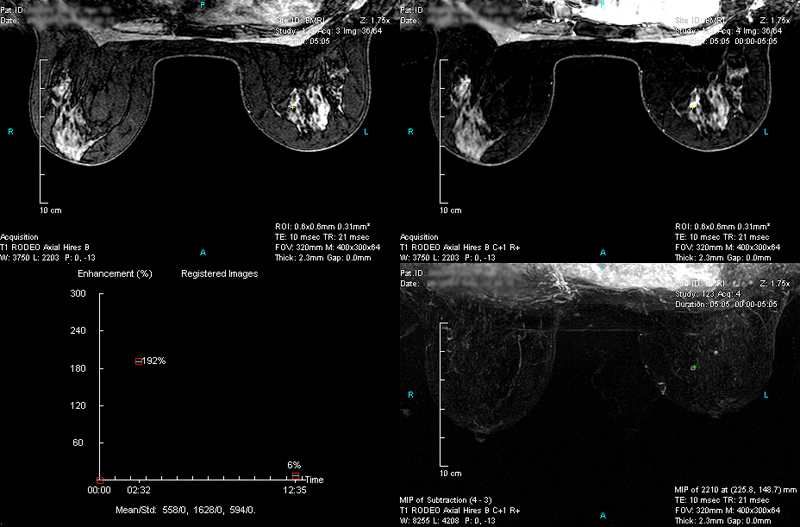

Case 3 - Left breast with 2 cancer sites

(from left to right, top to down)

RODEO Pre (unspoiled), Registered 1st Post (spoiled), TIC of the 1st ROI and MIP of Subtraction.